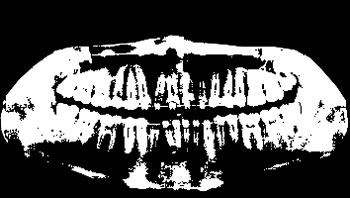

To thoroughly benchmark the methods studied here, the 1,500 images were distributed among 10 categories. The images were named, using whole numbers, in sequential order by category, aiming at not identifying the patients in the study. The process of categorizing the images was performed manually, selecting images individually, counting tooth by tooth, as well as verifying structural characteristics of the teeth. The images were classified according to the variety of structural characteristics of the teeth (see Table 5). Finally, the images were cut out to disregard non-relevant information (white border around the images and part of the spine) generated by the orthopantomograph device. After the clipping process, there was a change in the size of the images to 1991 ×\times 1127 pixels, but without affecting the objects of interest (teeth), as shown in Figure 2. The cropped images were saved on the new dimension to be used in the following stages, which will be presented in the next sections. Figure 3 shows an X-ray image corresponding to each of the categories of our data set.

Refer to caption

Figure 3: Examples of images from the data set categories of present work: (a) Category 1; (b) Category 2; (c) Category 3; (d) Category 4; (e) Category 5; (f) Category 6; (g) Category 7; (h) Category 8; (i) Category 9; (j) Category 10.